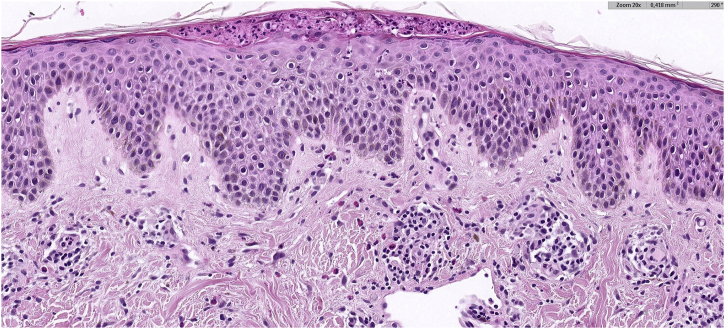

Fig. 2.

Hystopatology: Lymphocytic dermatitis with eosinophils, spongiosis, acanthosis, and a neutrophilic subcorneal pustule, findings consistent with a fully developed stage lesion of prurigo pigmentosa (Hematoxylin & eosin, ×20).